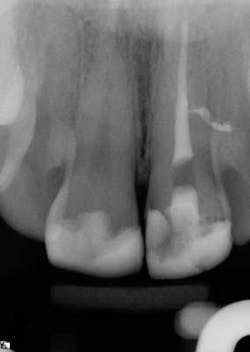

While mandibular incisors are my least favorite teeth to treat, the premolar teeth also provide significant reason for concern as they have highly variable anatomy. The maxillary first and second premolars will have one, two, or three roots and canals. (Figure 3) Maxillary premolar teeth have the smallest mean apical dimension at the apex (11) and the most variable anatomy, with exception of third molars. (12,17) The roots are often very thin, and a bulbous clinical crown may have significant taper to a thin root in the mesial-distal dimension that is broad in the facial-lingual dimension. It is not uncommon to see mesial-distal fractures in maxillary first or second premolars. Maxillary second premolars may have more curvature in the apical portion of the root when the sinus is close to the root ends. (Figure 4)

following root canal treatment in teeth Nos. 4 and 5. An angled

radiograph indicated a high probability for an untreated canal in

tooth No. 4 and as a result, this tooth was retreated.

increased concern about the anatomy in tooth No. 5. This tooth

was subsequently retreated due to persistent symptoms.

were present in both Nos. 4 and 5 following the initial root

canal treatment.